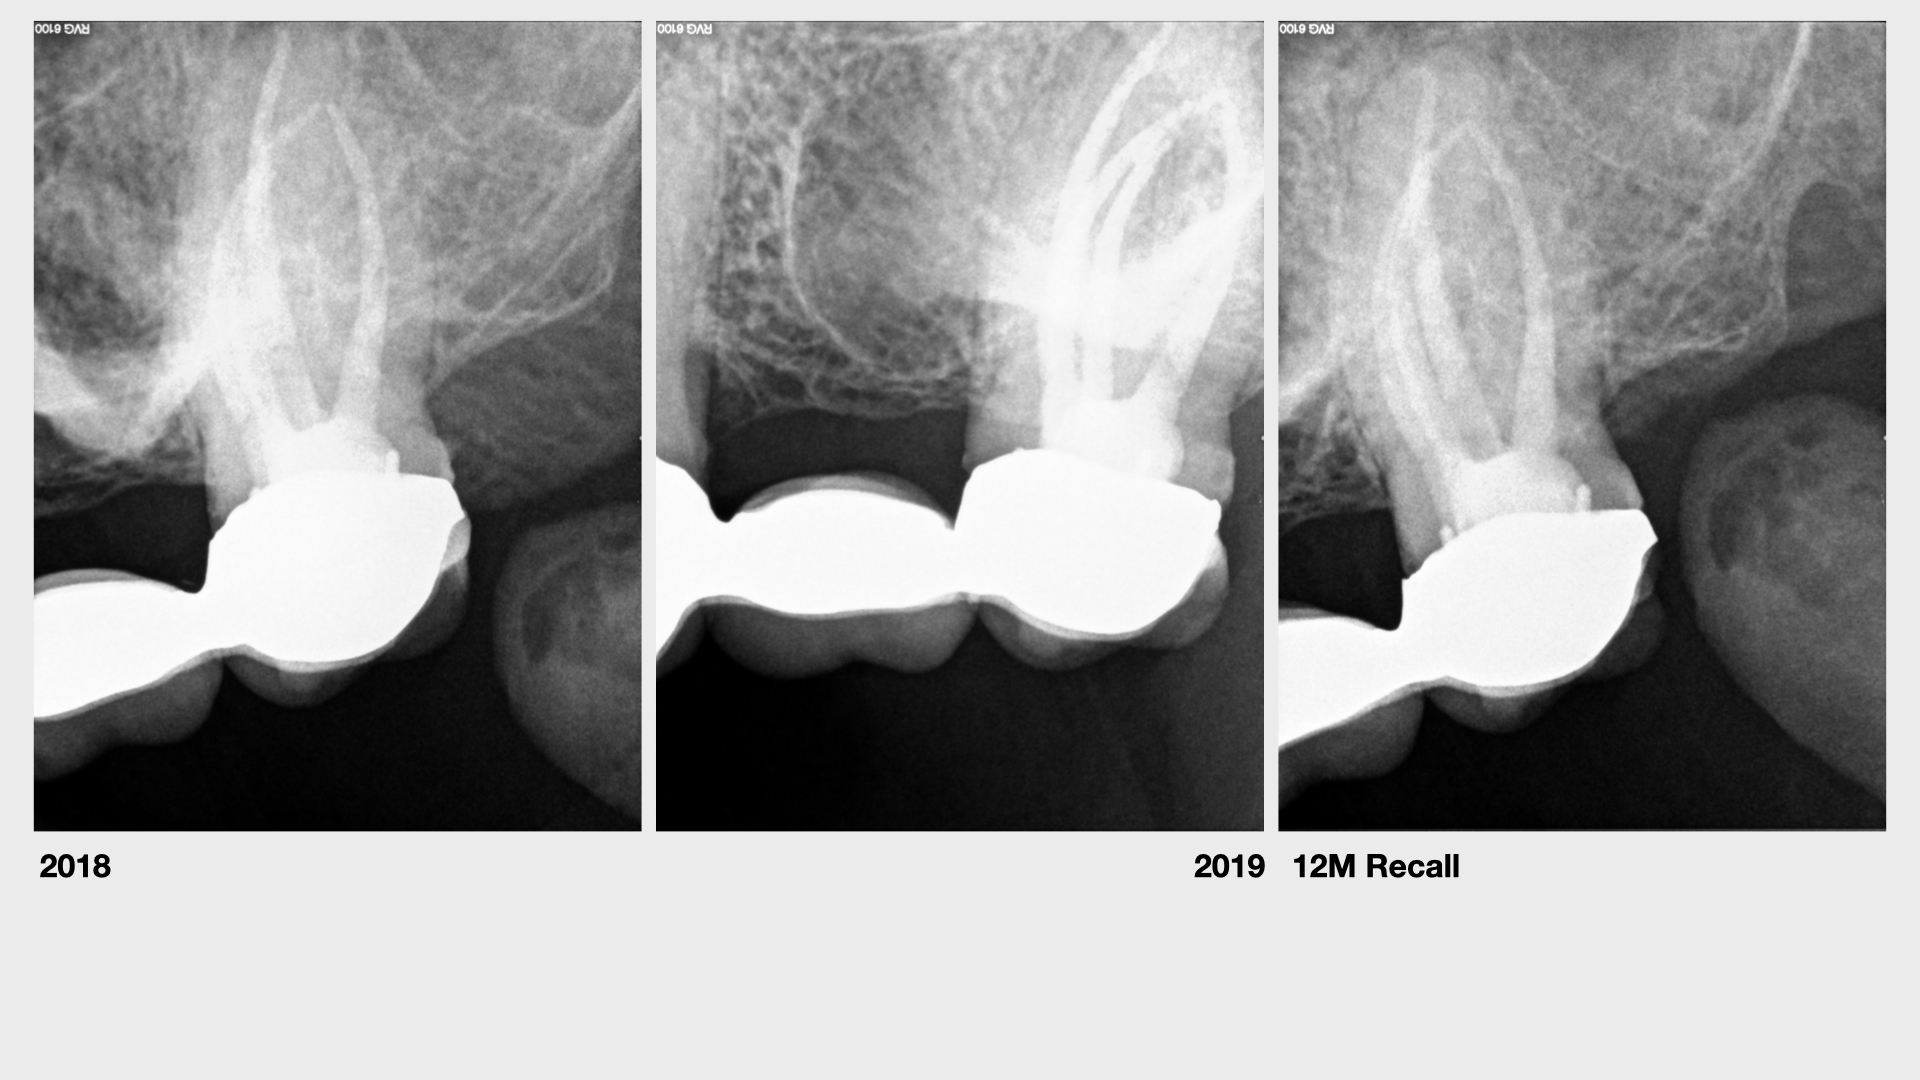

27 P. apicalis